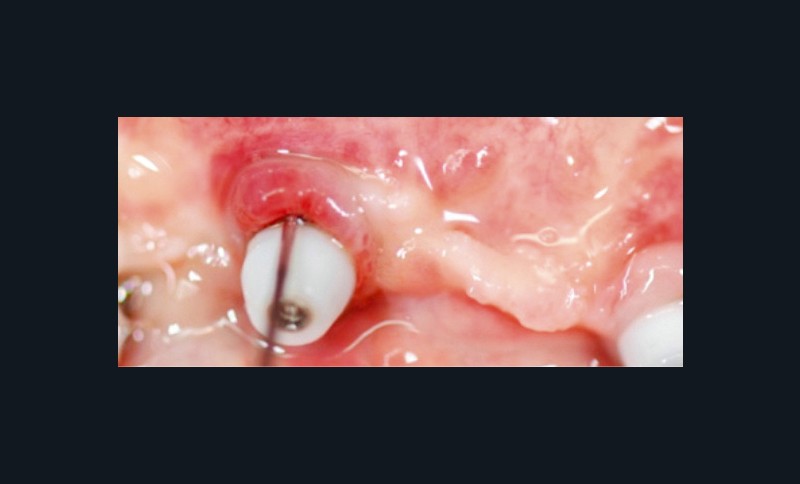

La plaque bactérienne (biofilm) pénètre et envahit les tissus muqueux autour des implants dentaires (fig. 3). S’installent une inflammation de la muqueuse péri-implantaire et la perte progressive et asynchrone du tissu osseux [4]. La péri-implantite survient au cours des premières années de mise en fonction de l’implant [4] et en l’absence de traitement, la maladie progresse (fig. 4) de manière non linéaire et rapide [4, 7].